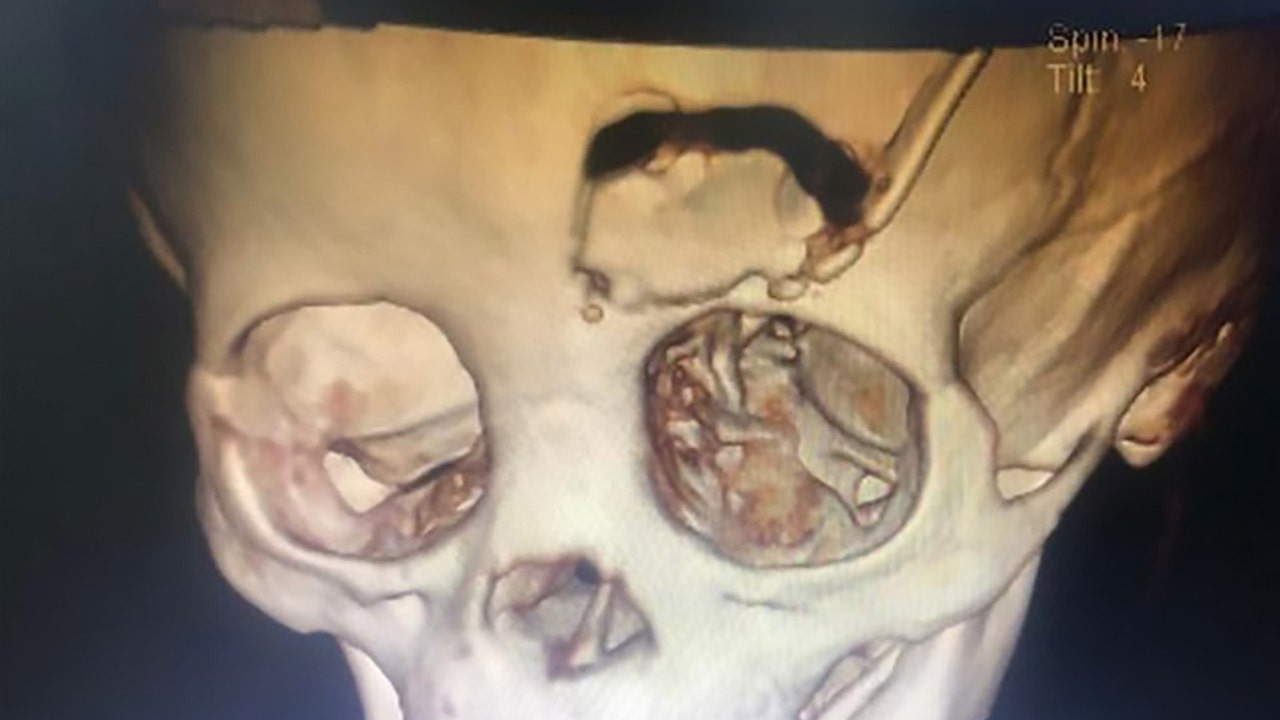

A scan showing a bone flap created to retrieve the skull fragment in the boy's head (AsiaWire)

The 14-month-old was admitted to Dongguan Children’s Hospital in China on Jan. 17, where doctors ordered scans which revealed that the impact of the pencil had fractured a piece of his left eye socket, AsiaWire reported. While the pencil managed to evade the eyeball, the piece of the fractured skull wound up lodged behind his left eye socket.